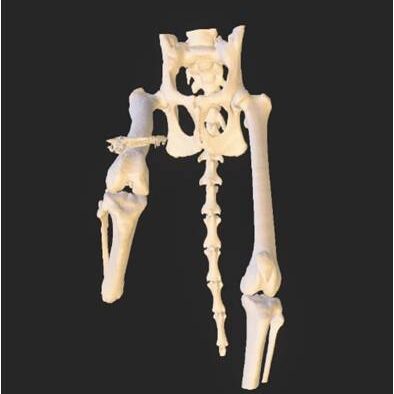

Το εμφύτευμα τύπου ITAP (Intraosseous Transcutaneous Amputation Prosthesis) είναι μία καινοτόμος μέθοδος που χρησιμοποιείται για την δημιουργία τεχνητού μέλους σε περιπτώσεις ακρωτηριασμένου άκρου ενός κατοικίδιου. Η χρήση της προσθετικής χειρουργικής έρχεται για να δώσει λύσεις σε περιπτώσεις ακρωτηριασμού μελών προσομοιώνοντας την φυσική κινητικότητα με κάποιο τεχνητό μέλος. Το κόκαλο αναπτύσσεται, ή «οστεοενσωματώνεται» στο σημείο όπου ενώνεται με το εμφύτευμα ΙΤΑΡ, αφήνοντας μόνο ένα μικρό μεταλλικό τμήμα να ξεπροβάλλει. Εκεί μπορεί να συνδέεται ή να αποσυνδέεται ένα τεχνητό μέλος (πατουσάκι) κατά βούληση.

Υπάρχουν διαφορετικοί τύποι εμφυτευμάτων τύπου ITAP, ανάλογα την έκταση της ακρωτηριασμένης περιοχής, καθώς και την θέση αυτού, δηλαδή πρόσθιο ή οπίσθιο άκρο.

• Φυσικά πρωτότυπα των οστών όπου θα εφαρμοστεί το εμφύτευμα.